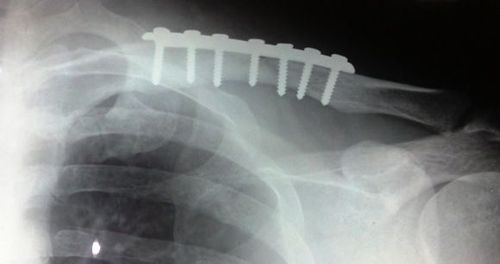

Ngoài ra, bệnh nhân sẽ được chụp X-quang ở tư thế thẳng và một tư thế đặc biệt dành cho xương đòn để bác sĩ có thể đánh giá xem hai đoạn xương gãy có bị xê dịch trước sau hay không.

Phẫu thuật giúp nắn chỉnh xương tốt hơn, nhưng chi phí sẽ cao hơn và để lại sẹo sau khi mổ. Bệnh nhân phải trải qua hai cuộc mổ: lần đầu để sửa xương và lần thứ hai để lấy dụng cụ y tế ra. Tuy nhiên, sau phẫu thuật, bệnh nhân có thể vận động sớm hơn so với điều trị bảo tồn.